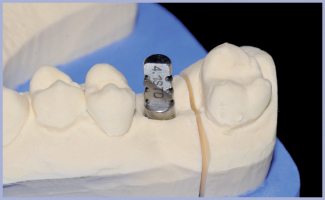

Paziente di sesso maschile di anni 36, nessuna notizia anamnestica particolarmente rilevante. La radiografia pre-operatoria dell’area edentula da riabilitare, zona 16, mostra una scarsa disponibilità ossea verticale. Si esclude un intervento di mini rialzo di seno optando per l’impiego di un impianto corto 6.5 Exacone® (fig. 1) in tecnica monofasica poiché, al momento dell’inserimento, la stabilità primaria è eccellente. Dopo cinque mesi si procede alla rimozione del tappo di guarigione, alla verifica della guarigione dei tessuti ed alla presa dell’impronta in polietere (Impregum™ 3M ESPE). Sopra il transfer si posiziona l’analogo con il suo pin. Le componenti (transfer, analogo, ecc.) che si utilizzano sopra l’impianto corto sono le stesse dell’impianto 4,1, come si evince dalle foto (figg. 3-6). Dopo aver sviluppato il modello, condizioniamo il gesso per migliorare i volumi del dente che andiamo a progettare, non solo per una questione estetica ma anche per un maggior comfort per il paziente (figg. 7, 8). Si procede alla digitalizzazione del modello master tramite scansione con dispositivo Inlab Sirona (fig. 9).

- Fig. 15 – Primo adattamento del manufatto al moncone MultiTech